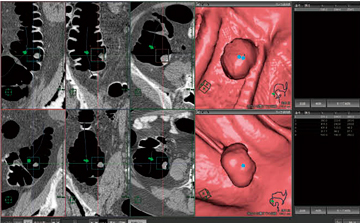

大腸抽出においては,形状や位置関係から大腸領域を自動的に推測し,大腸のみを抽出することが可能である(図1)。

図1 全自動解析処理